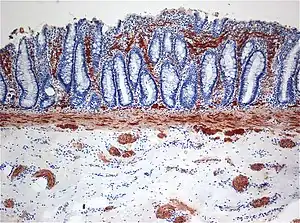

A falta de células ganglionares no plexo mioentérico e submucoso está associada à Doença de Hirschsprung.[7] Com a Doença de Hirschsprung, o segmento sem neurônios (aganglionar) fica contraído, fazendo com que a seção proximal normal do intestino se distenda com fezes. Acredita-se que esse estreitamento do cólon distal e a falha de relaxamento no segmento aganglionar sejam causados pela falta de neurônios contendo óxido nítrico sintase.[7]

A característica mais citada é a ausência de células ganglionares: notadamente em homens, 75% não têm nenhuma no final do cólon (retossigmóide) e 8% não têm células ganglionares em todo o cólon. A seção aumentada do intestino é encontrada proximalmente, enquanto a seção aganglionar estreitada é encontrada distalmente, mais perto do final do intestino. A ausência de células ganglionares resulta em uma superestimulação persistente dos nervos na região afetada, resultando em contração.

O diagnóstico definitivo é feito por biópsia por sucção do segmento estreitado distalmente.[26] Um exame histológico do tecido tem por objetivo mostrar a falta de células nervosas ganglionares. As técnicas de diagnóstico envolvem manometria anorretal,[27] enema baritado e biópsia retal. A biópsia retal por sucção é considerada o padrão ouro internacional atual no diagnóstico da Doença de Hirschsprung.[28]